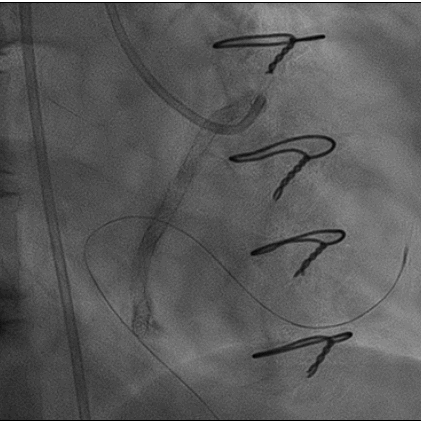

造影: